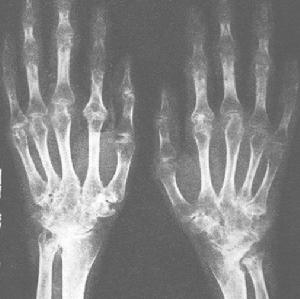

3類風濕性關節炎:主要有反覆多關節遊走性與對稱性疼痛,棱形腫脹,晨起出現關節活動僵硬,需活動後才可緩解,時間>半小時,可伴有發熱,疲憊,食少,面色蒼白,貧血。關節腫脹疼痛多與天氣變化有關,後期可出現關節變形,雙腕及手向尺側偏斜畸形,雙膝畸形腫脹,屈伸受限,各關節活動範圍逐漸減少。X光片表現為受累關節間隙模糊,骨端破壞,關節間隙變窄甚至融合。因此後期患者關節活動障礙,且服藥對於改善關節功能較差,需行關節置換術治療以恢復關節功能。